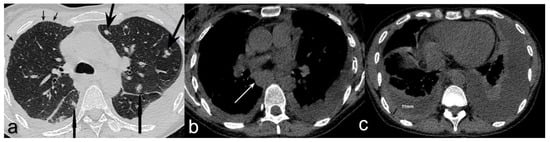

Figure 2. Axial non-contrast chest CT showed (a) multiple bilateral lung nodules (big arrows) and foci of thickened interlobular septa (small arrows); (b) enlarged subcarinal lymph nodes (white arrow); (c) right-sided pleural effusion with pleural thickening (measured) and left-sided pleural effusion partially compressing underlying lung parenchyma. Enlarged left supraclavicular and hepatic lymph nodes were found in the ultrasound examination. The overall clinical and radiologic appearance was suggestive of a lymphoma. On the day of admission, the patient developed fever of 40 °C. Sputum, blood, and urine cultures were taken—all turned out to be negative. Neither Legionella antigen in urine sample nor CMV antigen in blood were detected. An HIV test was requested as a part of the differential diagnosis of lymphopenia and lymphadenopathy. Meanwhile, an empirical antibiotic therapy consisting of ceftriaxone and levofloxacin was commenced; it was soon extended by the inclusion of clindamycin because the patient continued to be febrile. Bronchoscopy was performed and it showed a scar from previous lymph node ulceration into the left upper bronchus; aside from this the macroscopic appearance of the airways was irrelevant. The fluid from bronchoalveolar lavage (BALF) was collected and cultured. Direct microscopic examination was negative for acid-fast bacilli, but molecular testing with GeneXpert MTB/RIF assay detected the presence of Mycobacterium tuberculosis complex DNA; no rifampicin resistance gene was found. At the same time, a positive result for HIV-1 test (Bio-Rad Geenius TM HIV 1/2 Confirmatory Assay) was obtained. Anti-tuberculous treatment was started with isoniazid, rifampicin, ethambutol, and pyrazinamide. Soon, the patient became apyrexial and CRP started to decrease gradually. Mycobacterium tuberculosis (MTB) strain, susceptible to all primary anti-TB drugs, was cultured from BALF after two weeks. At the time of HIV infection diagnosis, the CD4+ T-lymphocyte count was 107 cells/mm3, and viral load 13,846 copies/mm3. Antiretroviral therapy (ART) with emtricitabine, tenofovir, and dolutegravir was commenced 11 days after anti-TB treatment was started. It resulted in a gradual improvement in CD4+ cell count and viral suppression; after four months CD4+ T-lymphocyte count reached level of >400 cells/mm3. Both anti-TB and antiviral therapies were well tolerated. The four-drug anti-TB treatment was continued for two months and was followed by seven months of isoniazid and rifampicin. Follow-up chest HRCT showed the regression of mediastinal lymphadenopathy and significant improvement of parenchymal and pleural abnormalities. The series of sputum cultures for acid-fast bacilli was negative. Three years after the diagnosis of pulmonary TB and acquired immunodeficiency syndrome (AIDS), the patient remains in good condition and continues ART successfully in an HIV/AIDS-dedicated out-patient clinic. The reported patient with newly diagnosed HIV infection and pulmonary TB had no background chronic conditions and considered herself healthy until the unspecific chest and feet pains, mild dry cough, fatigue, and reduced appetite occurred. The symptoms of pulmonary TB are unspecific, and the most common include cough with scanty sputum, haemoptysis, dyspnoea, chest pain, low-grade intermittent fever, sweating, fatigue, and weight loss [10]. Pulmonary TB in HIV-positive people presents with similar symptoms, but lower CD4+ cell counts are associated with more severe systemic symptoms [9,11]. Typical chest X-ray findings in pulmonary TB are: upper lung zones patchy consolidations, cavitations, features of bronchial dissemination [12]. Such radiologic features were not found in the presented patient. Chest CT scan showed multiple small nodules with perilymphatic distribution, interlobular septa thickening, enlarged mediastinal lymph nodes, and bilateral pleural effusion. As the HIV status of the patient was not known at that time, the radiologists suggested lung involvement in the course of a lymphoproliferative disease. That impression was further augmented by the presence of abdominal and supraclavicular lymphadenopathy. Nonspecific symptoms, high inflammatory indices, the presence of lymphopenia, lymphadenopathy, and pulmonary and pleural lesions required broad diagnostic work-up. Testing for HIV and MTB gave the conclusive outcome, and pulmonary TB in the course of HIV infection was diagnosed. Radiologic phenotype of TB associated with HIV is similar to that without HIV co-infection when CD4+ cell count is high, i.e., >350 cells/mm3. In cases with lower CD4+ cell counts, the presentation of pulmonary TB is shifted towards atypical patterns, such as parenchymal consolidations affecting the middle and lower lung zones, miliary infiltrates, chest lymphadenopathy, and pleural effusion, as in the presented patient [6,7,8,9]. Lung disease in the late period of HIV infection may be caused by opportunistic bacteria, tuberculous and non-tuberculous mycobacteria, viral and fungal pathogens, but also by the spectrum of neoplastic disorders, such as non-Hodgkin’s lymphoma or Kaposi’s sarcoma [13]. They may present with pleural effusion and pulmonary nodular infiltrates [13,14]. Thus, the differential considerations in the reported patient should also include these neoplastic diseases. The bronchoscopy revealed no suspicious endobronchial lesions, and microscopic examination of BALF was negative for atypical or neoplastic cells. Finally, therapies targeted at TB and HIV resulted in resolution of lymphadenopathy. An additional difficulty in diagnosing TB in PLWH is a higher rate of smear-negative disease. For this reason, molecular WHO-recommended rapid diagnostic tests, such as GeneXpert MTB/RIF assay, are recommended as an initial test rather than smear microscopy or culture [3]. Anti-tuberculous treatment regimen and its duration in drug-susceptible TB in PLWH are the same as in TB without HIV co-infection [5]. ART should be started as soon as possible (within two weeks of initiating TB treatment) regardless of CD4+ cell count, with the only exception being TB meningitis, where it should be delayed for four weeks if CD4+ < 50 (100) cells/mm3 [5]. The risk of death in people co-infected with HIV and TB is reportedly two to five times higher than in HIV-infected patients without TB with matched CD4+ cell counts, irrespective of ART, effective TB treatment, and good access to healthcare [15,16,17]. There is the evidence that TB directly contributes to mortality in HIV-infected patients, rather than simply presenting as a marker of advanced immunodeficiency [18]. Delayed TB diagnosis, i.e., after ≥1 month of symptoms duration, increases the risk of death [19], and the first 3 months after TB diagnosis seem crucial for survival in PLWH [15]. A TB recurrence rate is higher in PLWH than in people without HIV—4.5 vs. 1.9 per 100 person-years, respectively [20]. The presented patient remains well three years after diagnosis of TB and HIV co-infection, with viral suppression on ART and no signs of TB recurrence. Populations with high prevalence of HIV infection include men who have sex with men, intravenous drug users, people in prisons and other closed settings, sex workers, and transgender people [21]. In summary, co-infection with HIV may change the clinical phenotype of TB, leading to diagnostic problems and delayed treatment. The highest level of vigilance with regard to TB is recommended in PLWH. Moreover, each newly diagnosed TB patient should be tested for HIV.